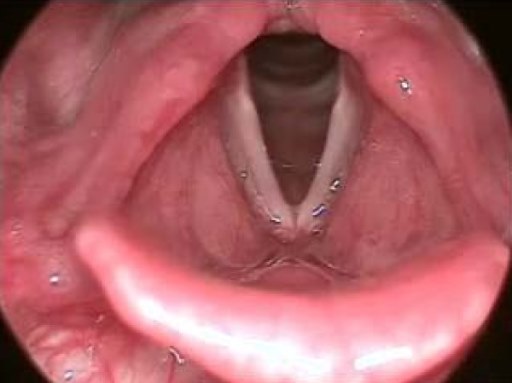

What is a laryngospasm?

- Closure of the vocal cords where the larynx closes the glottis by contracting.

- It is the body’s natural response to prevent substances from entering the lungs.